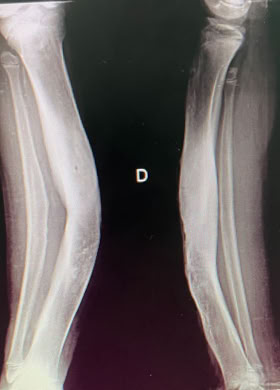

Traumatología

Gracias a COEM es posible realizar una traumatología del siglo XXI en una comunidad que de otra forma solo tendría acceso a una medicina medieval